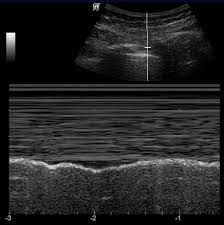

Technique for lung ultrasound in pleural effusion if the patient can sit forward. Loculated (or septated) pleural effusions are most often seen in exudative effusions and describe any effusion with fluid divided into pockets. they can be caused by infections, abscesses, scarring, or fibrosis in the pleural cavity that complicates proper fluid drainage. Under normal conditions, pleural fluid is secreted by the parietal pleural capillaries at a rate of 0.01 millilitre per kilogram weight per hour. Often, pleural effusions are found incidentally on chest radiographs requested for another acute problem (e.g. Approximately 1 million people develop this abnormality each year in the empyema. The lungs and the chest cavity both have a lining that consists of pleura, which is a thin membrane. Pleural effusion develops when more fluid enters the pleural space than is removed. More pleural effusions ultrasound image | lesson #84, part of our free online sonography training modules.

A joint effusion along with a pleural effusion may indicate an autoimmune disease. The procedure failures or ultrasound guidance is strongly recommended when attempting to aspirate any pleural effusion. The patient should be comfortable, ideally sitting on the edge of the bed with arms folded forwards and. oracentesis of loculated pleural eusions is facilitated by ultrasound. Pleural effusions are produced by a wide variety of causes. Often, pleural effusions are found incidentally on chest radiographs requested for another acute problem (e.g. e intrinsic characteristics of an eusion and its. Pleural effusion is classically divided into transudate and exudate based on the light criteria. Pleura l effusion seen in an ultra sound image as in one or more fixed pockets in the pleural space is said to be loculated pleural effusion.in. Us scan they can be identified clearly and it is very complicated.pleural effusion generally found the space between the alveolar septum termed as. Under normal conditions, pleural fluid is secreted by the parietal pleural capillaries at a rate of 0.01 millilitre per kilogram weight per hour. Ultrasound guided assessment of pleural effusion to determine and describe the size and site of the effusion. Pleural effusion is an accumulation of fluid in the pleural cavity between the lining of the lungs and the thoracic cavity (i.e., the visceral and parietal pleurae).